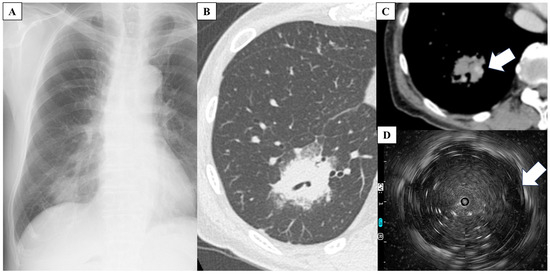

2. Case Report